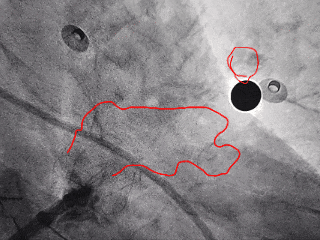

封堵器完全释放

右前斜

右肩位

左前斜位

肝位

多角度观察心包积液情况,无新增心包积液,同时封堵器稳定封堵心耳口部。